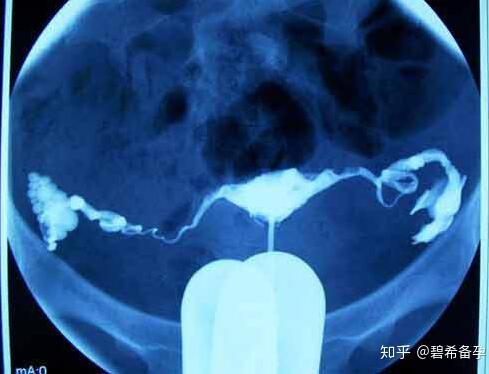

子宮輸卵管造影(Hysterosalpingography,HSC),簡(jiǎn)單說(shuō)就是,先用導(dǎo)管向子宮腔及輸卵管注入造影劑,然后通過(guò)拍片,根據(jù)顯影情況了解輸卵管是否通暢。

在簡(jiǎn)單消毒后,醫(yī)生會(huì)往宮腔內(nèi)插入導(dǎo)管并注入適量的造影劑,然后觀察造影劑在輸卵管及盆腔內(nèi)的顯影情況。